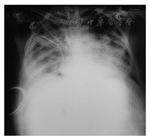

患者病情趋于稳定,2017年1月9日突发憋气,双肺新发满布哮鸣音、多发湿啰音,床旁胸部X线片提示急性肺水肿(图3),予床旁血液滤过(超滤量4 L)、无创通气,呼吸困难可好转。2017年1月10日出现发热,体温38.7 ℃,伴氧合下降,动脉血气示呼吸衰竭(pH 7.319,二氧化碳分压49.4 mmHg,氧分压53.7 mmHg,碳酸氢根24.6 mmol/L,乳酸0.9 mmol/L),考虑呼吸肌受累不除外,合并肺部感染,此后氧合迅速下降,难以维持,患者家属拒绝有创抢救,患者于2017年1月10日死亡。